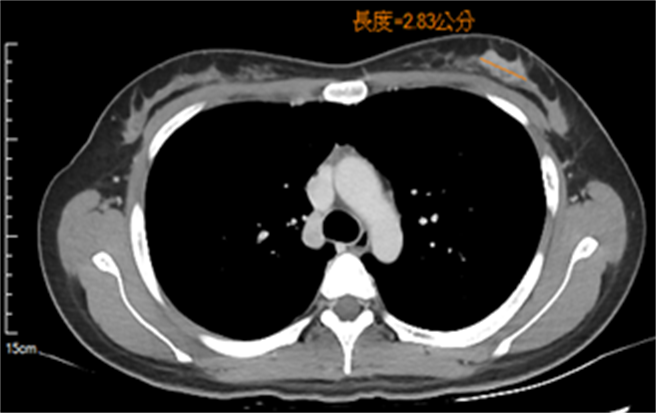

新竹台大分院指出,张女就诊并进行乳房超音波后,外科医师告知该肿块有可能为恶性,建议做乳房摄影及切片检查。经切片后,确诊为乳癌,并从电脑断层发现,张女左边腋下有肿大的淋巴结,所幸无其他远端转移。

张女随后立即被转至肿瘤医学部门诊,透过医病共享决策后,决定先安排前导性化疗及标靶治疗,经6次治疗后,追踪超音波发现肿瘤几乎消失,近期已准备入院接受乳癌切除手术。